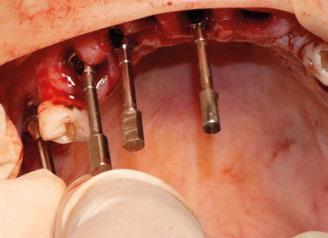

Ejecución técnica quirúrgica mediante férula guiada Bajo anestesia infiltrativa realizamos extracciones atraumáticas de todas las piezas a excepción de los dientes que actúan como anclaje o pilares para la fijación de la férula quirúrgica (Figuras 20 y 21). Seguidamente insertamos la férula comprobando una buena adaptabilidad y estabilidad

Figura Figura en posición ideal. Figura Figura

34 CIENCIA Y CLÍNICA. Caso clínico Gaceta Dental · N o 366 | Mayo 2024

Figura

de dientes estratégicos para fijar la férula quirúrgica.

Figura 23. Férula quirúrgica inferior. Figura 24. Fresado guiado con férula y cucharilla. Figura 20. Extracciones dentales. 21. Conservación Figura 22. Férula quirúrgica superior. Figura 25. Inserción de implante RSX de Bego a través de férula quirúrgica. Figura 27. Conexión de pilar angulado multiplus sobre implante. Figura 26. Implante insertado en lecho a través de férula quirúrgica. Figura 28. Muestra del perfecto paralelismo tras la colocación de pilares angulados multiplus. Figura 29. ScanBody sobre pilares transepiteliales.

(Figuras 22 y 23). Se realiza fresado transgingival mínimamente invasivo y guiado hasta la inserción de los implantes, siguiendo el protocolo preestablecido e indicado (Figuras 24 a 26).

Durante la colocación de los implantes comprobamos una inserción con torque superior a 35 N/cm2

Retiramos la férula y comprobamos una correcta estabilidad primaria mediante mediación de valores

ISQ favorables en la mayoría de los implantes. Seguidamente se extraen los dientes remanentes que han actuado de medio retentivo para la férula quirúrgica.

Dentro de la fase quirúrgica propiamente dicha, una vez terminada la inserción de los implantes y

comprobada su estabilidad primaria, colocamos pilares transepiteliales

Multiplus para registrar una impresión digital mediante escaneado sobre ellos (Figuras 27 a 29)